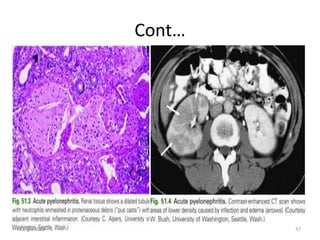

Cont…

Clinical manifestations of acute pyelonephritis

• symptoms of cystitis

• fever (>38ºC),

• chills,

• flank pain,

• costovertebral angle tenderness, and

• nausea/vomiting .

• sepsis, multiple organ system dysfunction,

shock, and/or acute renal failure.

• Symptoms may vary from a mild illness to a sepsis

syndrome with or without shock and renal

failure.

• Bacteremia develops in 20–30% of cases of

pyelonephritis.

• Pyuria is almost always present, but leukocyte casts,

specific for UTI, are infrequently seen.

Xanthogranulomatous Pyelonephritis

• Xanthogranulomatous pyelonephritis is a poorly

understood, uncommon, but severe chronic renal

infection associated with obstruction of the urinary

tract.

• The renal parenchyma is replaced with a diffuse or

segmental cellular infiltrate of foam cells, which are

lipid-laden macrophages.

12/30/2022 58

• Pathogenesis appears to be multifactorial, with

infection complicating obstruction and leading to

ischemia, tissue destruction, and accumulation of

lipid deposits.

12/30/2022 59

• The urine culture is usually positive with E. coli, other

gram-negative bacilli, or S. aureus.

• CT shows an enlarged nonfunctioning kidney, often

the presence of calculi and low-density masses

(xanthomatous tissue).

• Broad-spectrum antimicrobials are indicated, but

total or partial nephrectomy is usually necessary for

cure.